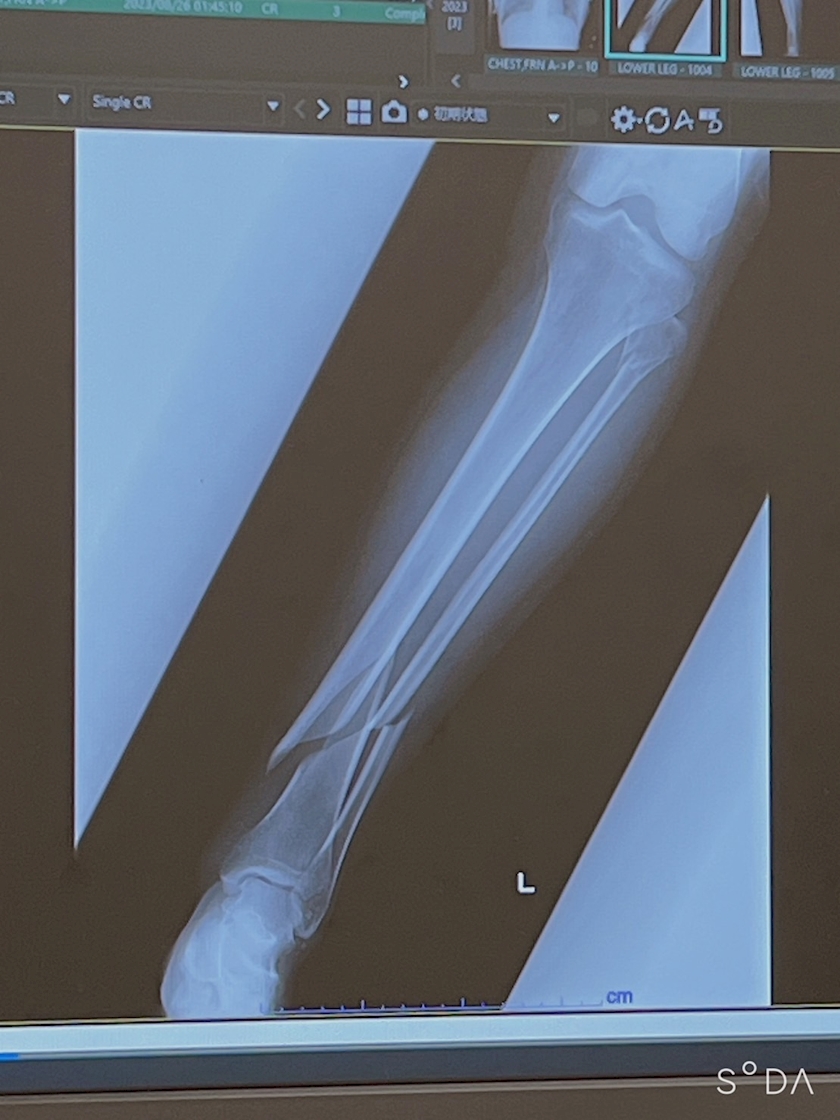

折れた足がくそくそ痛くて震えてる午後

昨日からなーんか足が痛くて😂

骨ついてるのに!!!

腱がおかしいのかもと、、、、

あと、やっぱり足庇って変な歩き方してるから本来使わない筋に力とか入って

違うとこが痛みだしてるんかも

でも折れ方は綺麗